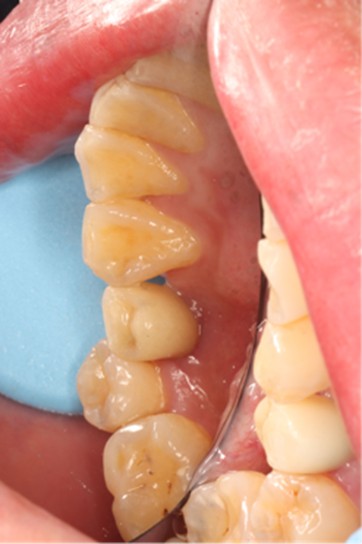

November 23, 2025: Implant follow-up examination. The implant surgical site showed excellent healing, with no abnormal bone density around the implant and satisfactory osteogenesis. The third-stage impression taking was implemented. The panoramic radiograph below confirmed the complete seating of the implant impression coping.

December 4, 2025: Definitive crown delivery. The margin of the implant-supported crown exhibited optimal adaptation.

Pre- and Post-Restorative Comparison